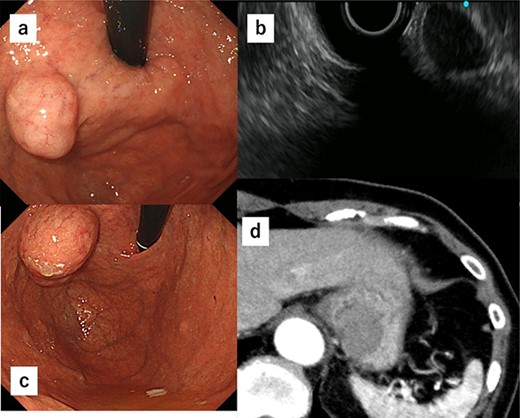

A 74-year-old woman who experienced epigastric discomfort 4 years ago visited our gastroenterology department. Physical examination and laboratory tests revealed no abnormal findings. A submucosal tumor measuring ∼2 cm in diameter was found at the posterior wall of the upper body of the gastric body near the EGJ by upper endoscopy, and endoscopic ultrasonography revealed a gastric hypoechoic tumor from the fourth layer, suggesting GIST (Fig. 1a and b). It was followed up because of its small size. The tumor grew in size gradually, and the patient was referred to our department. The tumor increased in diameter by ∼1 cm over 1 year (Fig. 1c). Computed tomography (CT) revealed an intraluminal growth type submucosal tumor measuring 3.5 cm in diameter and no metastasis (Fig. 1d). After biopsy, the tumor was classified as group 1 (i.e. normal tissue and non-neoplastic lesions).

(a) A submucosal tumor measuring ∼2 cm is found at the posterior wall of the upper body of the gastric body near the EGJ by upper endoscopy. (b) Endoscopic ultrasonography shows a gastric hypoechoic tumor from the fourth layer suggesting GIST. (c) The tumor shows increase in size by ∼1 cm compared with 1 year ago. (d) CT reveals an intraluminal growth type submucosal tumor measuring 3.5 cm in diameter and no metastasis.